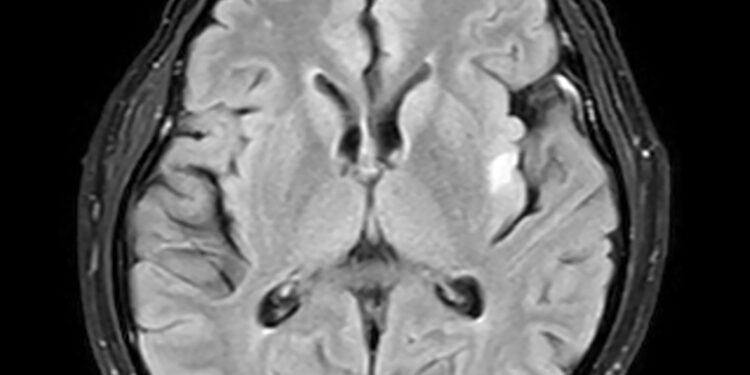

• Smegenų vaizdavimo tyrimai, pavyzdžiui, magnetinis rezonansas (MRT)